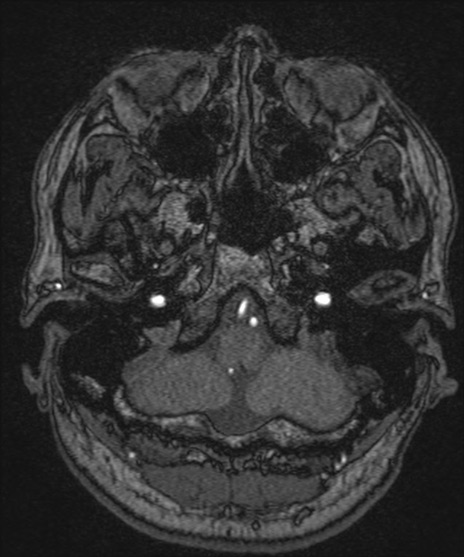

【頭部】TIPS症例12 MRI(MRA元画像)

【症例】40歳代男性

松果体にあるものはなに?